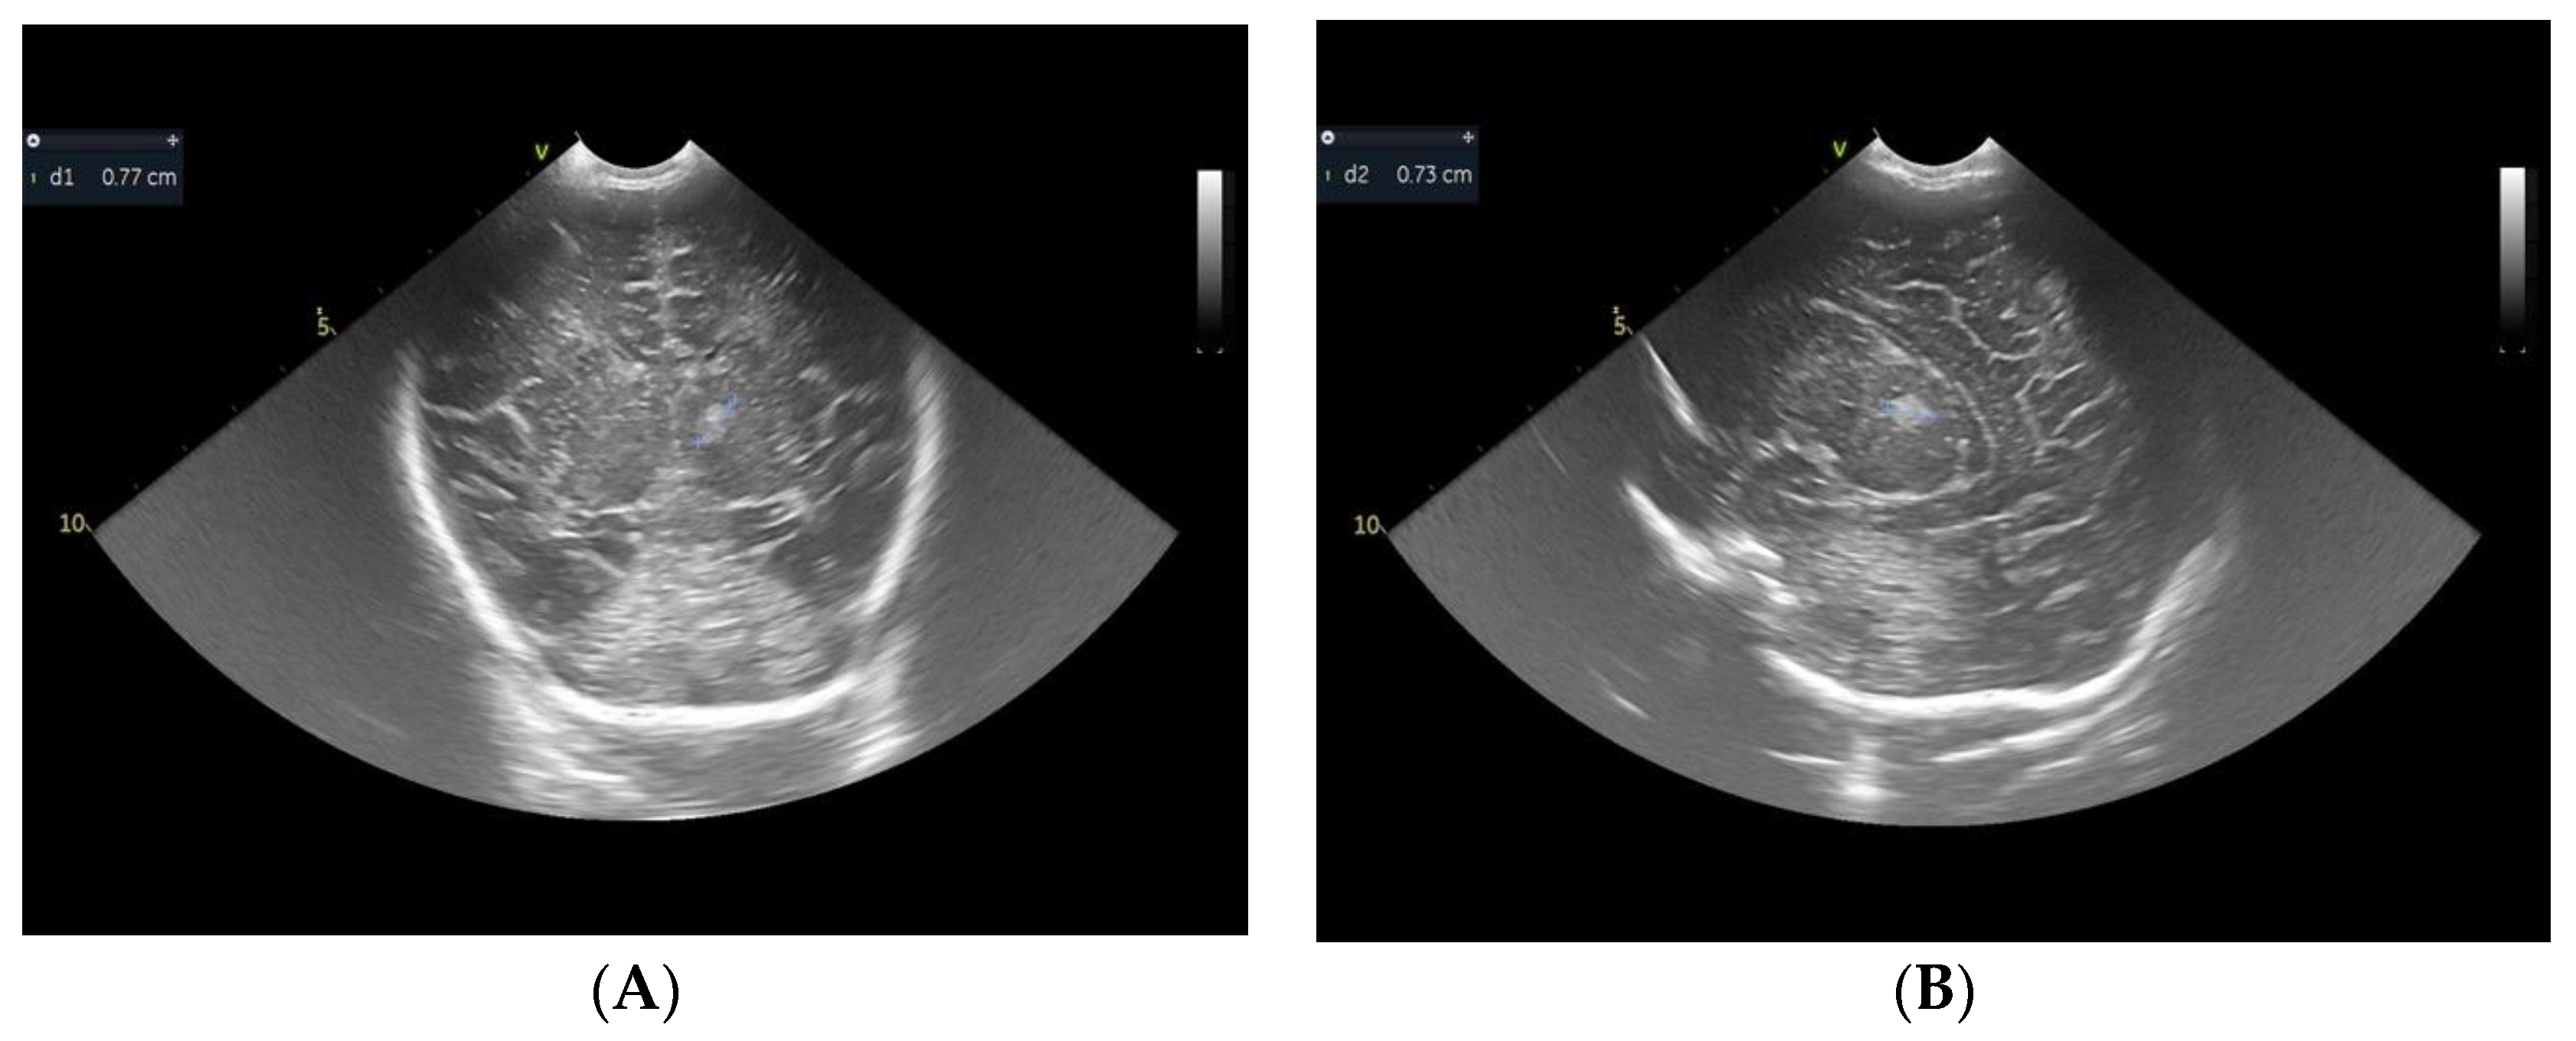

2. Case Report